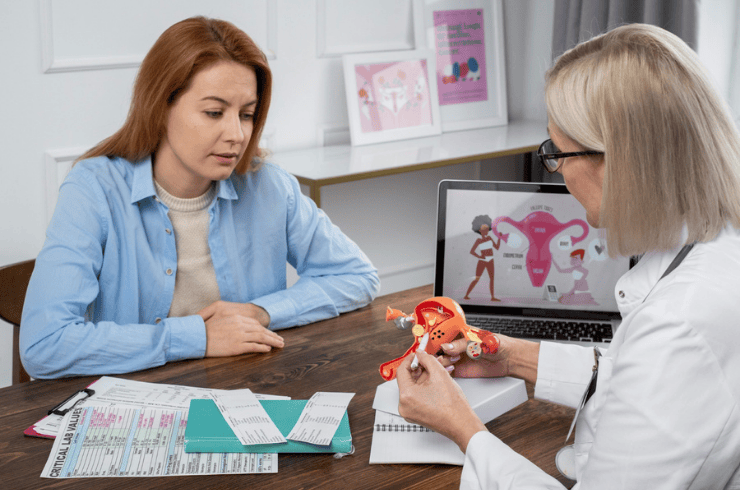

Compassionate fertility evaluation and treatment support for couples planning a healthy pregnancy.